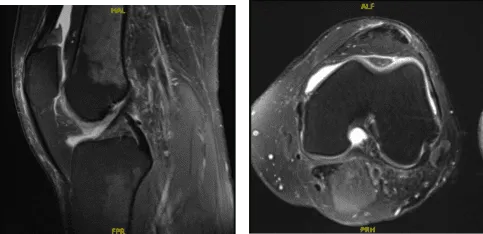

La hinchazón ha disminuido. Se revisaron y discutieron resonancias magnéticas, en las que los resultados mostraron un defecto condral de grosor total de 9 x 6 mm en la porción media del cóndilo femoral medial. Área focal de fisuración condral y pérdida de cartílago de espesor parcial en la troclea central. Menisco medial y lateral intacto.

MRI-3T Rodilla izquierda sin contraste